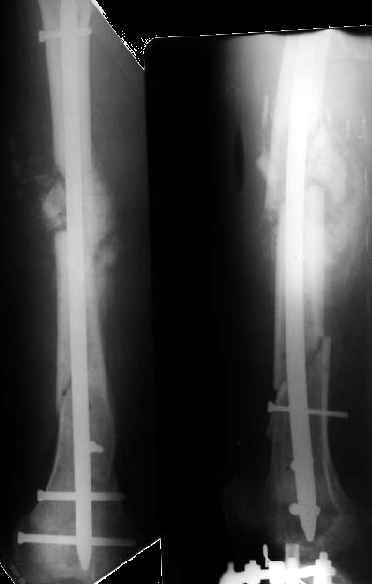

Как я уже сообщал, пациент поступил к нам в пятницу на прошлой неделе.

Сегодня сделана операция. Из бедра минимально инвазивно удалены пластинки. Один винт на верхней пластинке оказался сломан, так что пришлось там сделать разрезик побольше, см 5.

Хотя и с трудом, но на бедре удалось сразу выполнить закрытый интрамедуллярный остеосинтез с минимальным рассверливанием.

На голени - чрескожная остеотомия малоберцовой кости, закрытая остеоклазия большеберцовой, дистракционный остеосинтез аппаратом.

В плане - востановление длины и оси голени, разработка движеий в колене. Не уверен, что удастся синтезировать голень стержнем при таком маленьком сгибании в коленном суставе.

Вальгусную деформацию голени уменшили , но все же есть. На бедре в области нижнего перелома остается умеренная варусная деформация. По данным снимкам точно сказать на солько остается общая деформация конечности представляется трудным.

S> Вальгусную деформацию голени уменшили , но все же есть.

Это же не окончательное положение. Сегодня начали тянуть темпом 2 мм/сут.

Мне кажется - скорее, вальгусная... На следующей неделе сделаем еще снимки с захватом коленного сустава, уточним.

План сейчас - восстановить длину и ось голени. Если колено градусов еще хоть на 20 согнется - заштифтуем, если нет - перемонтируем аппарат для окончательной фиксации. Потом отправим ближе к дому.